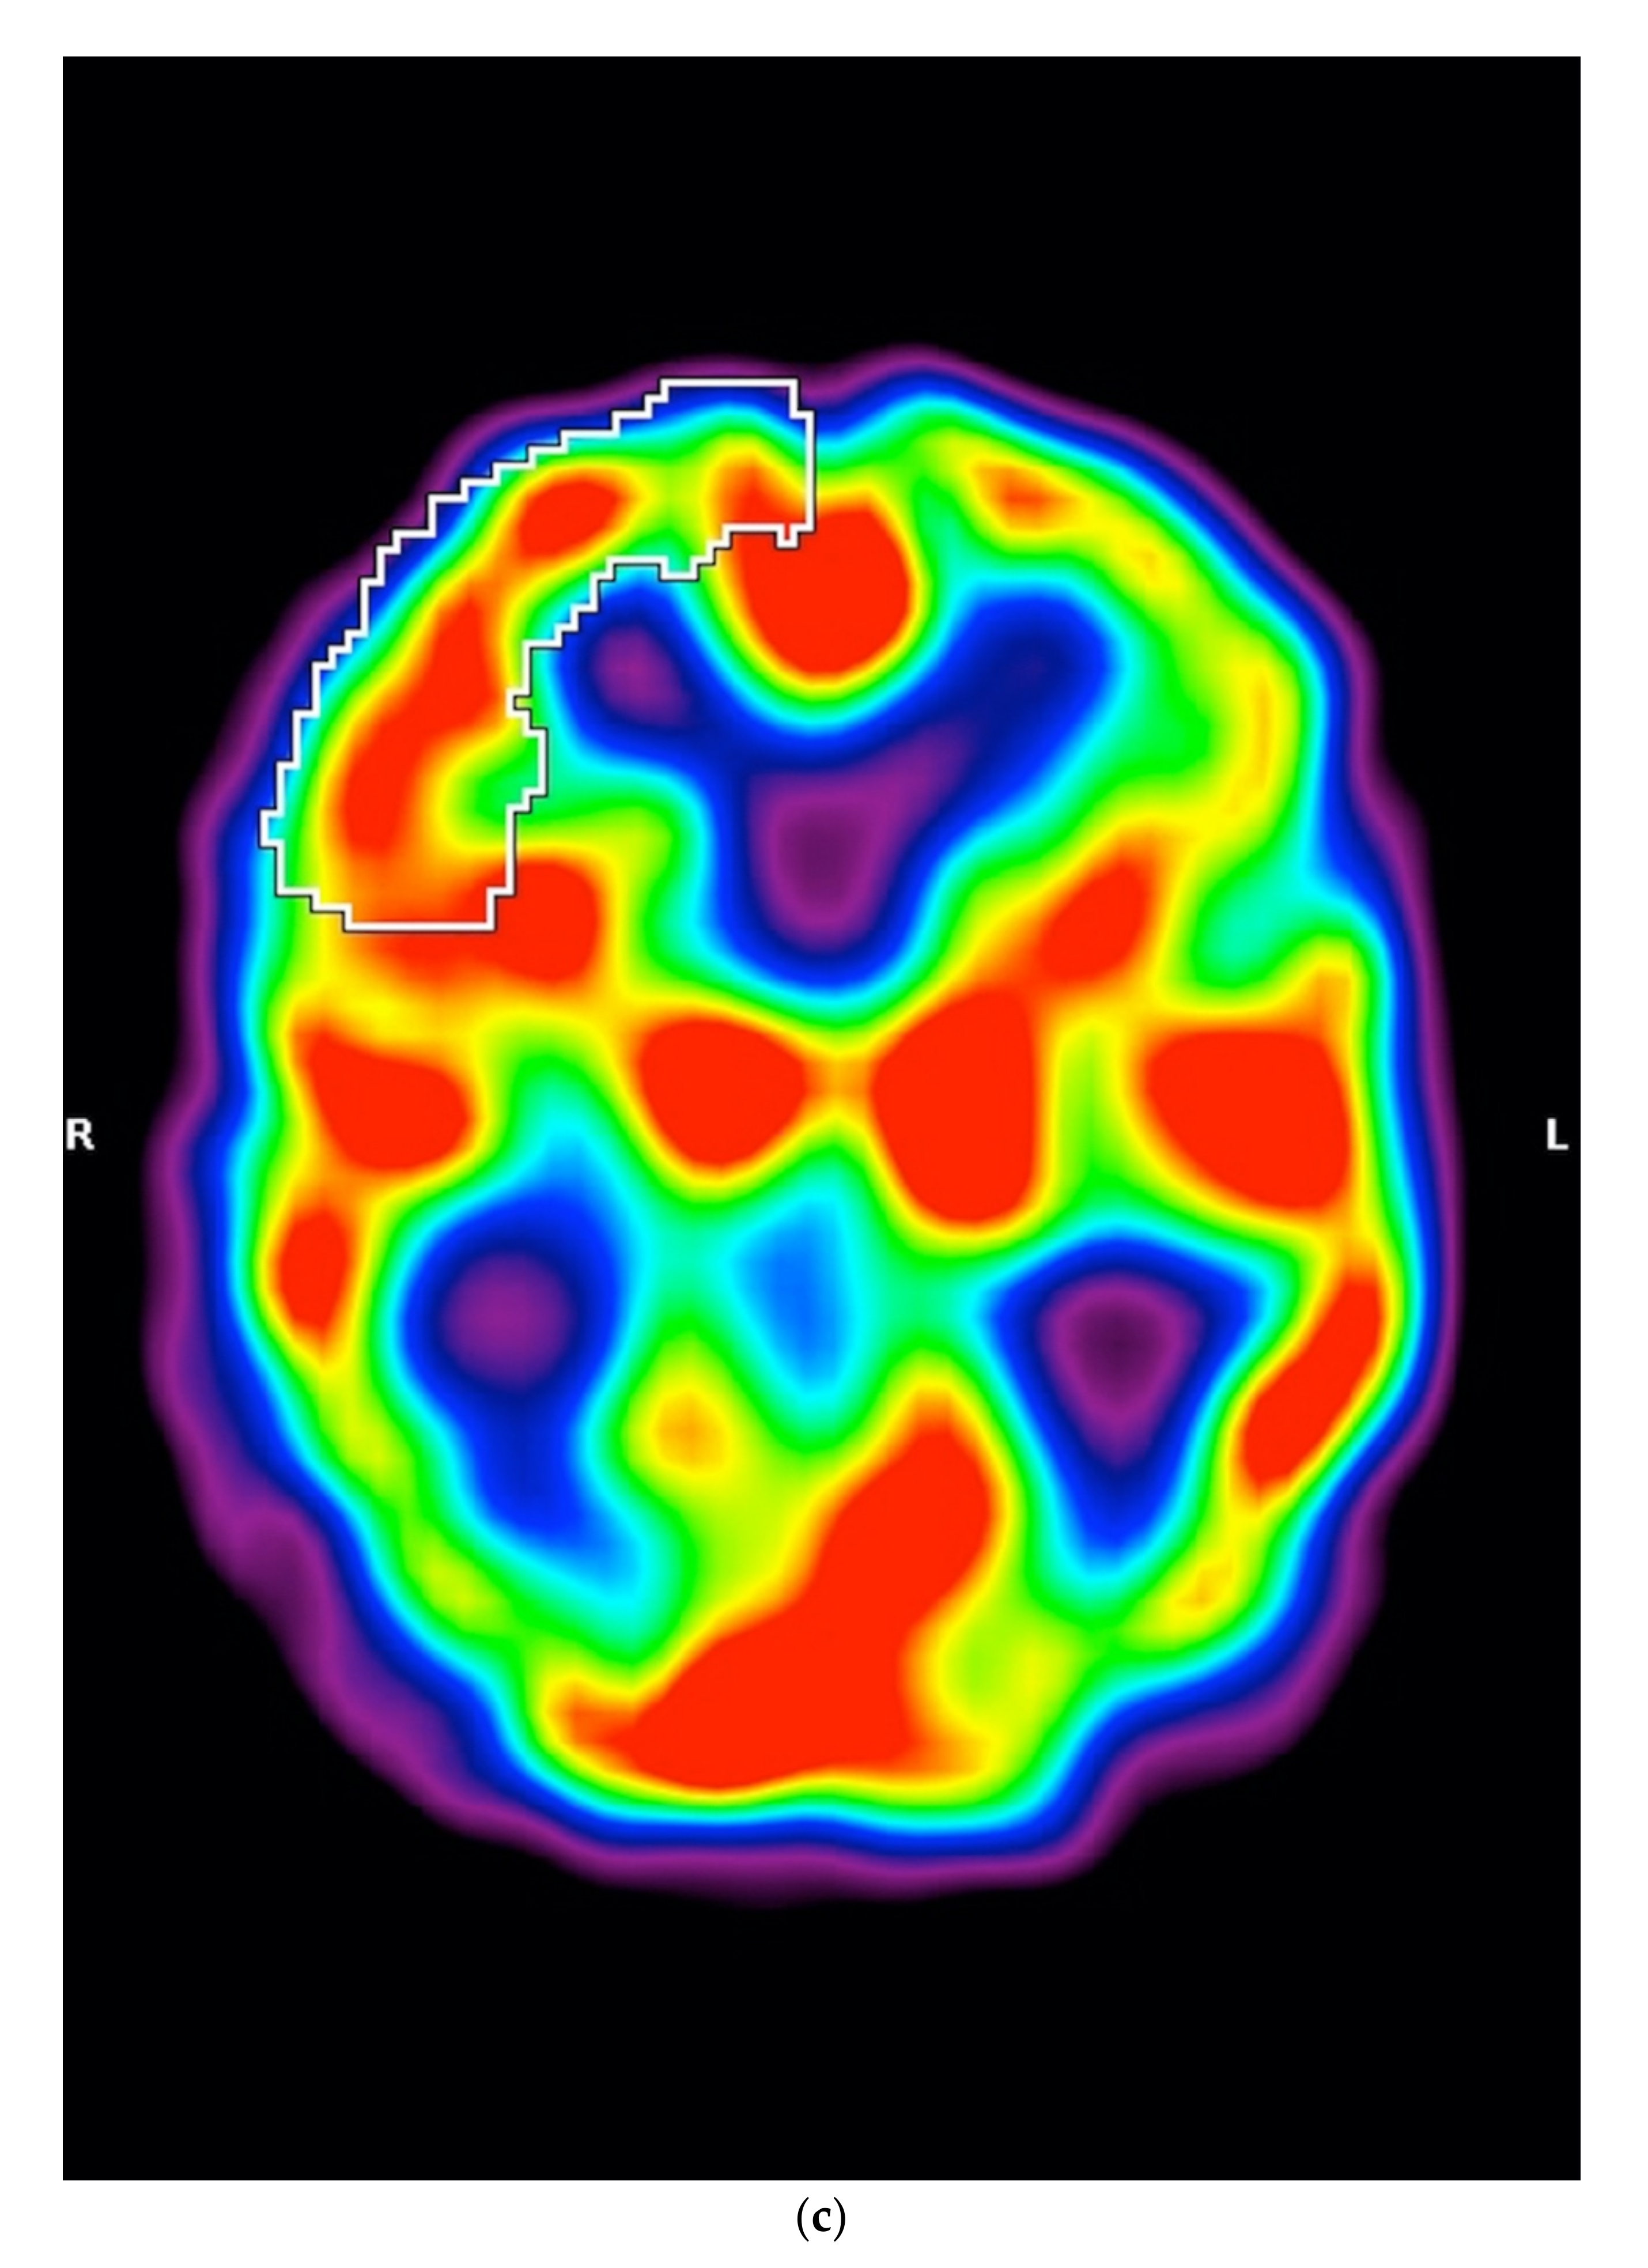

In SPECT imaging, patients with MSA-P had higher regional cerebral blood flow in the right frontal lobe (p = 0.0012) (Figure 2a–c).

Figure 2.

(a) Scatterplot presenting the significant differences between MSA-P and PSP-P in the right frontal lobe, (b) Axial 99mTc-HMPAO SPECT of a patient with PSP-P (frontal lobe hypoperfusion), (c) Axial 99mTc-HMPAO SPECT of a patient with MSA-P (without frontal lobe hypoperfusion).